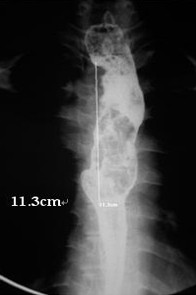

女,51岁,以“进行性吞咽困难1年”为主诉于2007年2月19日入院。钡餐造影、胃镜示食管上段占位性病变,确诊为食道鳞癌(图1),拒绝手术,行放疗+今又生治疗。食道镜下瘤内注射今又生,1×1012VP/次/周×6,放疗在今又生注射3 d后开始,采用常规分割三野等中心照射,剂量65cGY。治疗结束后4周,食管X线、胸部CT显示肿瘤完全消退(图4-5)。

治疗前